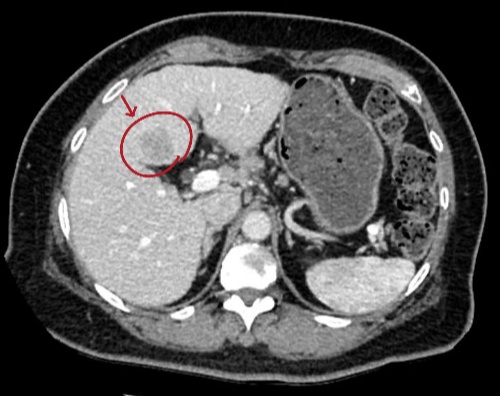

患者术前CT

利用术前CT,进行三维重建。